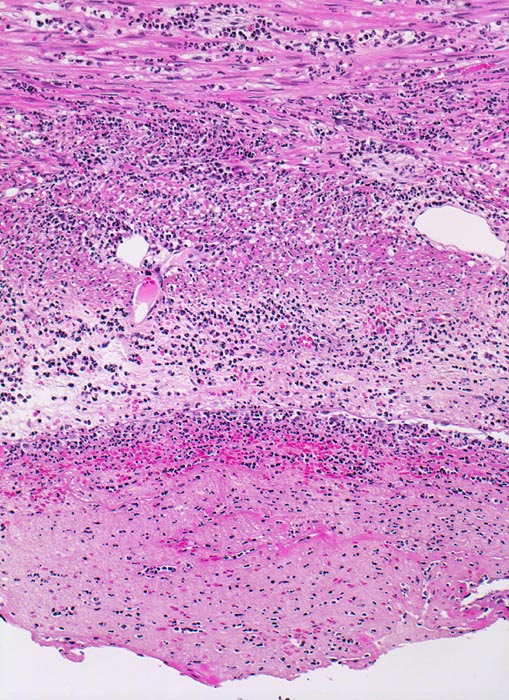

Morphologie: Das histologische Kriterium für eine akute Appendizitis ist die Infiltration der Muscularis propria mit neutrophilen Granulozyten.

Diffuse Durchsetzung der Appendixwand mit neutrophilen Granulozyten (phlegmonöse Entzündung).

Fibrinauflagerungen auf der Serosa durchmischt mit neutrophilen Granulozyten (fibrinös eitrige Peritonitis). Das sollte der Kliniker dem Pathologen mitteilen: